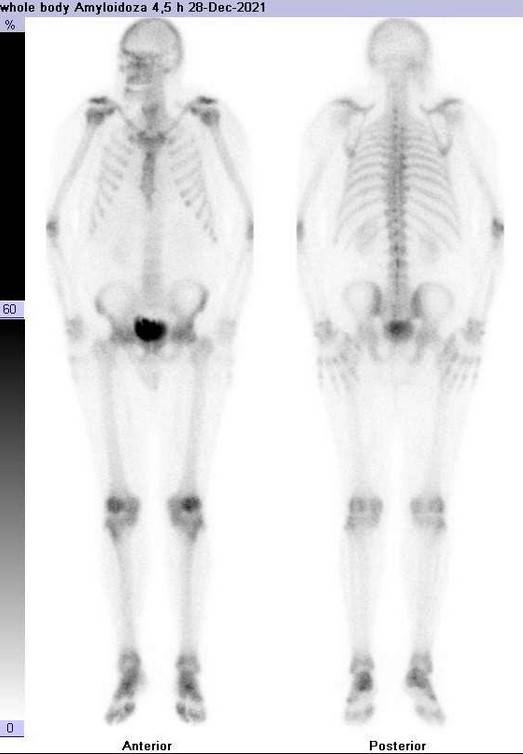

Badanie izotopowe

Badanie izotopowe SPECT stało się kluczową techniką w identyfikacji pacjentów z amyloidozą ATTR. W badaniu tym wykorzystuje się radioizotop technetu 99m w połączeniu ze znacznikami klasycznie stosowanymi w badaniu układu kostnego: jest to kwas 3,3-difosfo-no-1,2-propanodikarboksylowy (DPD) lub pirofosforan (PYP). Podczas badania izotopowego znacznik podaje się pacjentowi drogą dożylną i na podstawie odmiennego jego gromadzenia się w zdrowych i chorych partiach mięśnia serca dokonuje analizy uzyskanego w badaniu obrazu i potwierdza bądź wyklucza obecność amyloidozy.